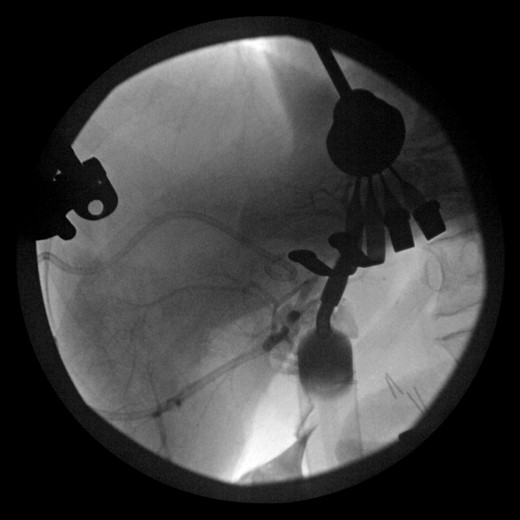

During this operation, the porta was dissected and the common and proper hepatic arteries were identified and preserved. We were unable to palpate the previously placed percutaneous biliary catheters due to the high placement above the hilum at the level of multiple clips. We transected the CBD distally and removed numerous clips, finally noting bile drainage, but were unable to identify a cholangiogram catheter. We then identified a second tubular structure more lateral to the duct. We elected to transect this tissue, identifying a second extrahepatic bile duct. The anterior percutaneous catheter was identified proximally within the duct. An on-table cholangiogram with fluoroscopy was performed noting two separate extrahepatic biliary systems, draining the right and left lobes of the liver, respectively (Figs 3 and 4). Both distal ducts were ligated to definitively close the orifice to the duodenum and prevent spillage. A Roux limb of jejunum was created and anastomosed in a retrocolic fashion to the two separate hepatic ducts at the level of the hilum. A drain was placed, and there was no evidence of bile leakage.

Intraoperative cholangiogram of the left ductal system through the extrahepatic left CBD.